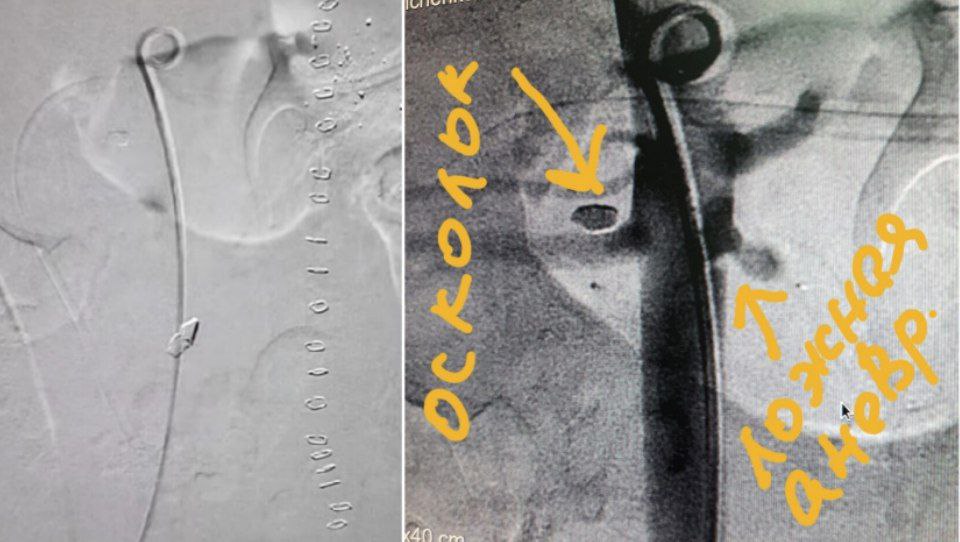

23-летний Алексей воевал в одной из самых горячих точек Украины – Бахмуте. Там он получил минно-взрывную травму с повреждением брюшной аорты. Об этом сообщает медик больницы имени Мечникова Олег Сергеев.

По его словам, получив такое ранение, большинство погибают сразу. Однако Алексею повезло. Медики больницы имени Мечникова провели уникальную операцию по пластике аорты и периоперационную интенсивную терапию.